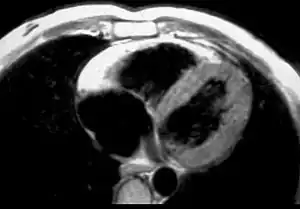

MRI in a patient affected by ARVC/D (long axis view of the right ventricle): note the transmural diffuse bright signal in the RV free wall on spin echo T1 (a) due to massive myocardial atrophy with fatty replacement (b).

In vitro MRI and corresponding cross section of the heart in ARVD show RV dilatation with anterior and posterior aneurysms (17-year-old asymptomatic male athlete who died suddenly during a soccer game).

Fatty infiltration of the RV free wall can be visible on cardiac MRI. Fat has increased intensity in T1-weighted images. However, it may be difficult to differentiate intramyocardial fat and the epicardial fat that is commonly seen adjacent to the normal heart. Also, the sub-tricuspid region may be difficult to distinguish from the atrioventricular sulcus, which is rich in fat.

Cardiac MRI can visualize the extreme thinning and akinesis of the RV free wall. However, the normal RV free wall may be about 3 mm thick, making the test less sensitive.